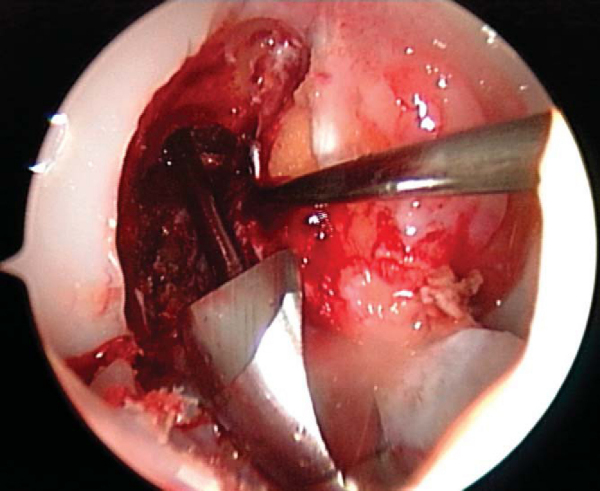

6. Graft Placement and Fixation

In the push-in technique, the graft is advanced through the tibial tunnel into the joint by use of a two-pronged pusher at the base of the femoral plug (

Fig. 60-9A

). A hemostat is placed through the inferomedial portal, grasping the femoral bone plug at the junction of the proximal and middle thirds. With the cortical surface of the femoral plug oriented posteriorly, the hemostat is used to guide the femoral plug into the femoral tunnel (

Fig. 60-9B

).

In the pull-through technique, the femoral bone plug suture is threaded through the eye of the Beath pin and retrieved proximally by pulling the Beath pin from its exit site in the thigh. The sutures of the femoral bone plug and the tibial bone plug are held taught as the graft is pulled through the knee. A probe or hemostat can be used to ensure proper orientation of the femoral bone plug as it enters the femoral tunnel.

Once the femoral bone plug is completely seated in the femoral tunnel, a nitinol guide pin (Linvatec, Largo, Fla) is placed into the femoral tunnel at the 11-o’clock position of the graft. The knee is flexed to 110 to 120 degrees, allowing easier passage of the guide pin within the femoral tunnel. The pin should be introduced without resistance; otherwise pin divergence should be suspected. A satellite pusher can be used to seat the femoral bone plug as needed. The tibial bone plug should be evaluated at this time for graft-tunnel mismatch. If the tibial plug is overhanging from the tibial tunnel, the graft can be removed and the femoral tunnel further recessed.

Femoral graft fixation is performed with an interference screw placed over the nitinol guide wire with the knee hyperflexed. The screw should be placed against the cancellous surface of the bone plug, away from the tendon insertion, to diminish the risk of graft injury or laceration. While tension is held on the tibial plug sutures, the knee is brought from 100 degrees to full extension to cycle the graft to ensure minimal graft motion as well as to assess impingement.

At this time, the tibial bone plug is externally rotated 180 degrees (toward the lateral side). This maneuver allows the tibial screw to be placed along the cortical surface and anterior. This screw placement avoids possible damage to the graft by a posteriorly placed screw with the knee in flexion as well as limits impingement that may occur with an anteriorized graft and a posteriorly placed screw.

The knee is placed in full extension, tension is held firmly on the tibial sutures, a nitinol wire is placed anterior to the tibial plug, and the interference screw is advanced and seated just below the cortical surface of the tibia. At this time, the arthroscope is placed into the knee, the ACL is visualized and probed to ensure proper tension, and a Lachman test and pivot shift test are performed (

Fig. 60-10